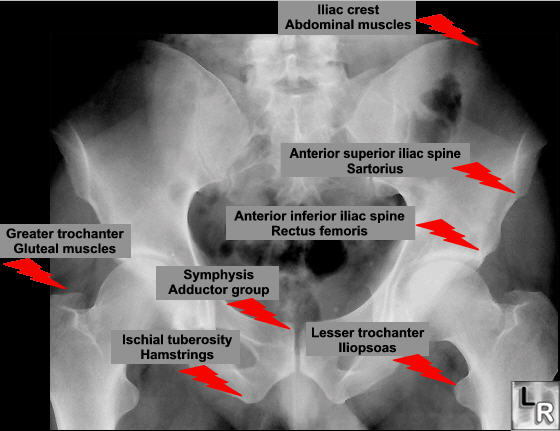

Any of the major muscle attaching to the pelvis or proximal femur may pull off at their attachment. This is classically a sporting injury, resulting from those resulting from extreme, unbalanced, often eccentric muscular contractions.

Anterior-Superior Iliac Spine Avulsion

This is the attachment of the sartorius and tensor fascia lata muscles.